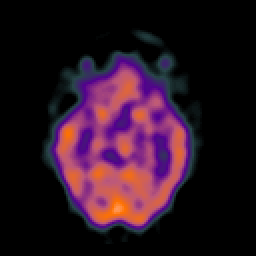

SPECT TC Study #7 -- Slice #23

[Home][Help][Clinical][Tour 1][Tour 2][Tour 3] Slice 23